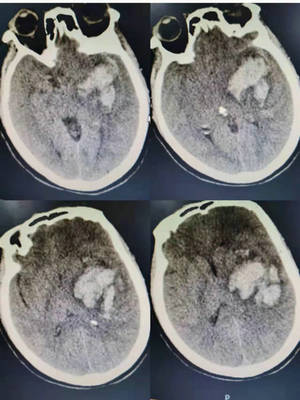

60岁的李阿姨平时有高血压病史,一直服用降压药,但是不规律。前几天,李阿姨突发头痛,恶心,言语不清,右侧肢体没有力气。半小时后,家人呼之不应,呼叫120将她送至betway在线登陆。入院后急查头颅CT,显示李大姨左侧基底节区脑出血,急诊科立即联系我院神经外科主任董伟前来会诊。

术前CT影像

此时,患者左侧瞳孔已散大,考虑已形成脑疝,病情十分凶险,随时有生命危险。董伟主任带领科室团队立即制定手术方案,因为患者脑出血部位很深,对血肿的清除要尽可能的彻底,董伟主任决定进行开颅显微镜下血肿清除加去骨瓣减压术,抢救患者生命。